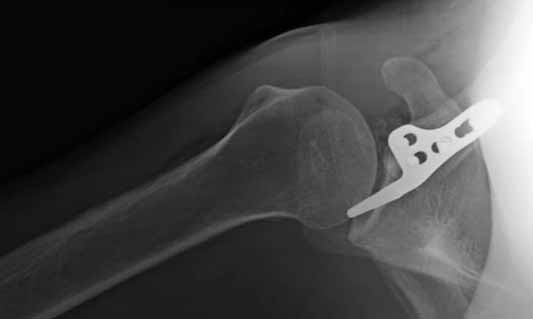

foto 4

4.JPG

14KB (14434 bytes)

На конференции EFORT в Копенгагене поднимался вопрос о пластинах для остеосинтеза ключицы с крючком. Не имею возможность осветить все что там услышал. Но у меня появилось понимание о импиджмент синдроме, о необходимой длине крючка, о правильном позиционировании пластины, о лизисе акромиона и т.д.

Мне кажется что если понять принципы, то можно использовать и короткую пластину. Что мы с успехом применяли раньше и применяем сейчас, но уже более осознанно. В вашем случае Серж, у меня стойкое ощущение, что необходима дополнительная иммобилизация, так как неправильно выбрано место введения крючка и при ранней нагрузке пластину просто вырвет. Если вам несложно не могли бы вы продемонстрировать прямую и боковую проекцию и в более хорошем качестве. ИМХО

На чем у Вас обосновано" стойкое ощущение, что необходима дополнительная иммобилизация, так как неправильно выбрано место введения крючка"?

Теоретически можно использовать и короткую пластину. Но на операции дистальный отломок( акромиальный конец ключицы ) был коротким и оскольчатым, поэтому крючок и использование там блокированных винтов в пластине было очень уместно. Доступ - "сабельный удар". Точка введения крючка - сразу сзади от ключично-акромиального сустава. Если честно - больше внимания уделяли репозиции отломков и адекватному расположению пластины на ключице :-) крючок проверяли на прочность фиксации за акромион и полный объем движений в плечевом суставе. После операции рука на косынке, нагрузку ограничили. Снимки есть в нормальном разрешении, но здесь "размер файла не превышал 75 кб." Если есть необходимость залью в пикассу...